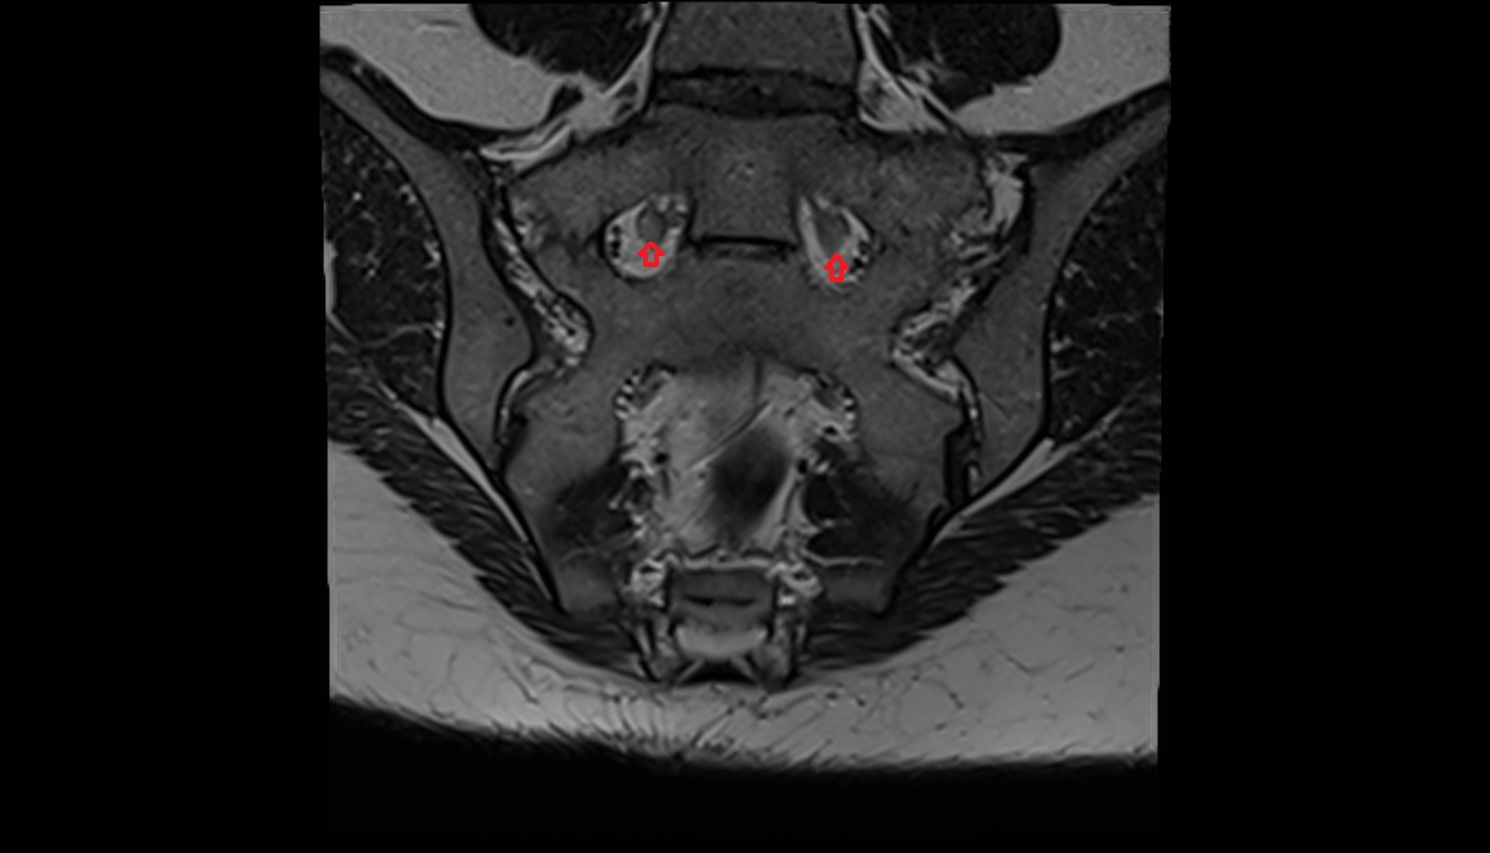

- Sacroiliac joint